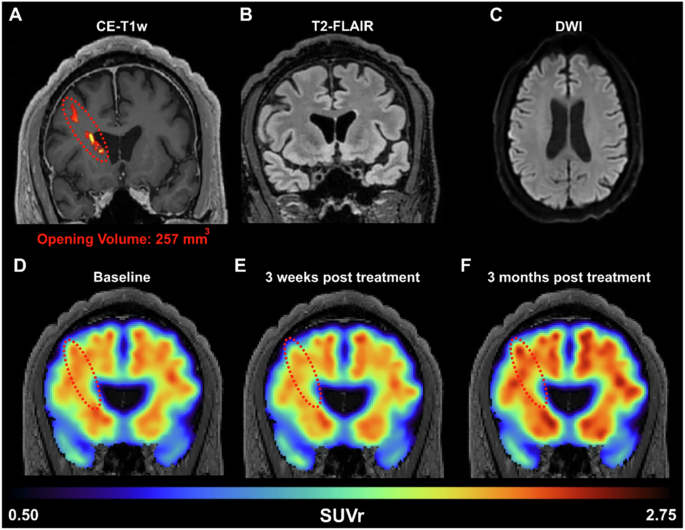

Compared to safety investigations performed using MRI, efficacy was assessed in every publication related to FUS + MB clinical trials. Each publication associated with clinical FUS-mediated BBB opening procedures included the acquisition of T1w-CE images to assess BBB permeabilization, Fig. 7. Pre-contrast-enhanced T1w images were acquired as a baseline before FUS treatment in 63% of studies related to FUS + MB clinical trials. Where reported, baseline T1w-CE images were acquired 1–2 days95,121,126,127,136,141 (6 publications), one week119,128,130 (3 publications) or one month123,124,129,130,134 (5 publications) before FUS procedures. After the sonication procedure, T1w-CE images were acquired as soon as possible, depending on the time required to transfer the patient from the FUS system to the MR scanner. The shortest time reported in the literature between the sonication procedure and T1w-CE acquisition was 10 minutes, with the contrast agent injected immediately after the MBs95,127. On average, T1w-CE images were acquired 55 minutes later (ranging from 15 minutes132 to 2 hours124) as reported121,124,132,136,140,141,142,143, with gadolinium contrast-agent such as Dotarem95,127, Gadovist118, diethylenetriamine pentaacetic acid129 or Gadovist137 injected 10-30 minutes before T1w-CE acquisition124,129,134,137,140,141.

A Amyloid PET signal reduction following FUS treatment in an early AD patient. BBB opening in the right prefrontal cortex was confirmed immediately after FUS exposure through contrast-enhanced T1-weighted (CE-T1w) MRI, revealing a contrast enhancement volume of 257 mm3 (red dotted oval). MRI safety scans, acquired on the day of treatment, including (B) T2-FLAIR and (C) DWI, indicate a safe opening without edema or hemorrhaging. The amyloid PET signal was measured at the (D) baseline pre-FUS, E 3 weeks, and (F) 3 months post-FUS. Within the treated frontal lobe, we detected a reduction of 1.8% in the SUVr 3 weeks after treatment, followed by a 5.9% increase in SUVr 3 months after treatment, all relative to the baseline scan. Figure reproduced with permission from ref. 19.

Finally, the reversibility of BBB opening was investigated in 77% of the studies. Reversibility was most often assessed 24 hours after sonication procedures (in 53% of the studies). If BBB permeabilization was still observed on MRI, a follow-up T1w-CE acquisition was performed 2–3 days after sonication128,133,134. Long-term reversibility was then assessed using T1w-CE acquisitions performed from two weeks to three months after sonication130,137,139.

Different radiotracers have been used to observe reductions in β-amyloid deposition in patients with Alzheimer’s and Parkinson’s diseases (Table 6). For example, [18 F]-Florbetaben was injected, and PET imaging was performed one week133, one month123, two months88,119, three months129,139, or 6-12135 months after FUS treatment. While the first study in Alzheimer’s patients did not observe any reduction in β-amyloid deposition after FUS + MB procedures88, later studies reported reductions in β-amyloid in both Alzheimer’s and Parkinson’s patients129,133. Specifically, for Alzheimer’s patients, the [18 F]-Fluorobetapir radiotracer was evaluated to assess decreases in amyloid burden near the targeted FUS area124,140, Fig. 7. PET imaging acquisitions were performed 3–8 months after FUS treatment, with only one study observing a decrease in β-amyloid deposition124.